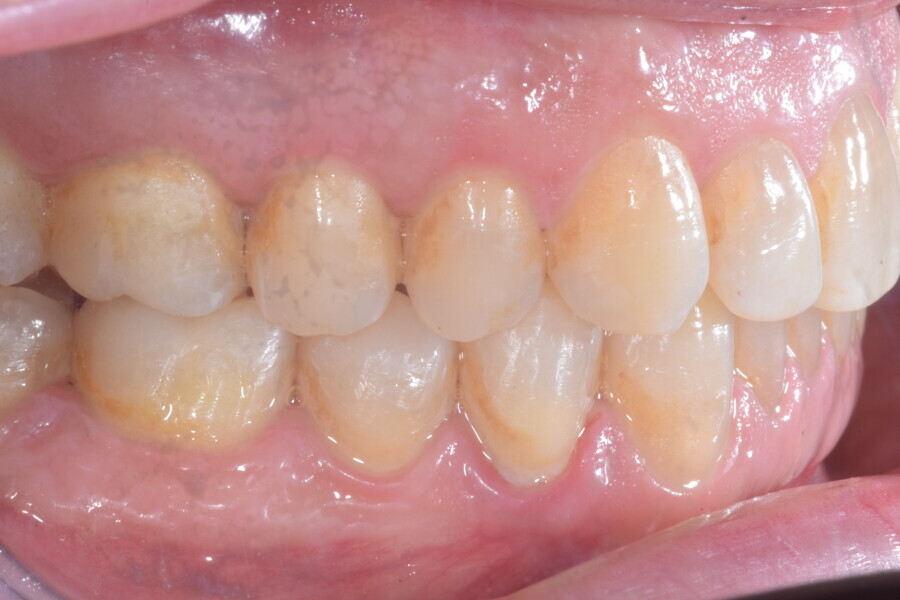

À la fin du traitement, on pouvait observer une relation de classe I des canines et des molaires, une légère augmentation de l’inclinaison des incisives supérieures (Ui-FH = 112°), une correction complète de l’inclinaison des incisives inférieures (IMPA = 97,09°) grâce à la vestibulo-version, et une légère amélioration de l’hypodivergence (SN-GoGn = 27°) résultant de l’extrusion relative des dents postérieures, et de l’utilisation d’élastiques de classe II — petite variation (1°) très intéressante compte tenu de l’âge du patient (Figs. 25–35). La ligne du sourire était harmonieuse et correspondait à une relation idéale entre les incisives supérieures et la lèvre inférieure. Le sourire avait été élargi grâce au contrôle du torque des segments latéraux et postérieurs.

La ligne du sourire était harmonieuse et correspondait à une relation idéale entre les incisives supérieures et la lèvre inférieure. Le sourire avait été élargi grâce au contrôle du torque des segments latéraux et postérieurs. La superposition des tracés céphalométriques montrait des changements intéressants induits par le traitement orthodontique (Figs. 36 et 37) :

Lors du suivi à un an, alors que le patient portait un appareil de rétention (appareil de rétention Vivera avec rampes d’occlusion, Align Technology), le résultat était stable et l’intercuspation était nettement meilleure (Figs. 38–42).